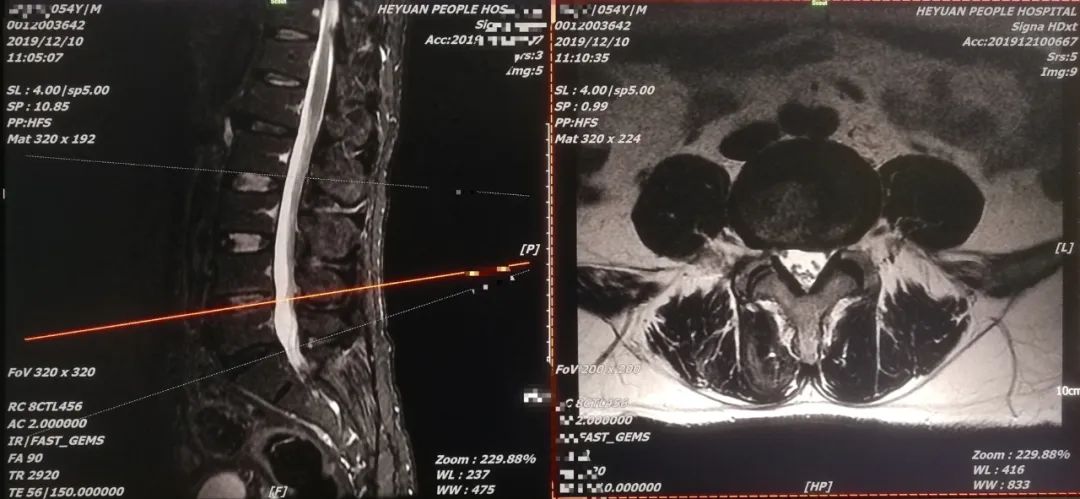

征得患者及家属同意,于4月22日,科室专家团队为该患者在局麻下实施微创椎间孔镜下腰4/5椎间盘突出摘除、神经根松解术。术后患者感觉腰腿疼症状明显改善,下肢抬高自如,取得满意效果。经腰椎MR复查,突出椎间盘组织完全摘除,目前患者已康复出院。

术后腰椎MR